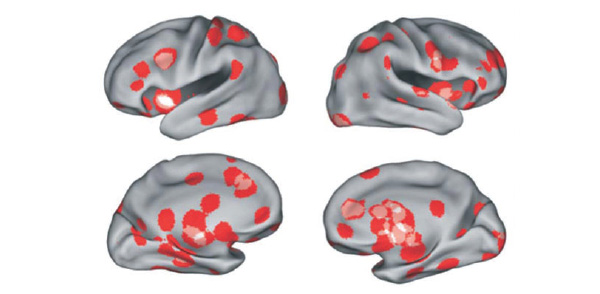

Нейробиологи из США и Швейцарии обобщили результаты шести исследований феномена любви, выполненных при помощи функциональной магнитно-резонансной томографии (фМРТ). Авторы пришли к выводу, что любовь — не просто «базовая эмоция», а комплексное явление, связанное с активностью многих отделов мозга, отвечающих за разные психические функции: чувство удовольствия, формирование привязанностей, мотивацию целенаправленного поведения, социальное познание и представление о самом себе. Области мозга, связанные со страстной влюбленностью и материнской любовью, пересекаются, но всё же имеют свою специфику.

Романтическая (страстная) любовь, или влюбленность, связана с комплексным возбуждением нескольких отделов мозга.

Во-первых, это дофаминэргические подкорковые области, отвечающие за положительное подкрепление («система награды»), чувство удовольствия, эйфорию. В этих областях много рецепторов дофамина и окситоцина (см.: Гены управляют поведением, а поведение — генами, «Элементы», 12.11.2008). Сюда относятся хвостатое ядро (caudate nucleus) и скорлупа (putamen). Это те области, которые возбуждаются под действием кокаина (потому что кокаин подавляет обратное всасывание дофамина нервными окончаниями, которые выделяют дофамин).

Во-вторых, при страстной любви возбуждаются островок (insula) и передняя часть поясной извилины (anterior cingulate cortex) — отделы, имеющие отношение к сексуальному возбуждению.

В-третьих, снижается возбуждение миндалины (amygdala; отвечает за страх, тревожность, беспокойство) и задней части поясной извилины (posterior cingulate cortex). По-видимому, передняя часть поясной извилины отвечает за переживание счастливой любви и сексуального возбуждения, тогда как ее задняя часть активизируется при переживании несчастной любви или горя от утраты любимого — например, у вдов, которым показывают фотографию недавно умершего мужа.

В целом характер специфического возбуждения подкорковых областей в ответ на стимулы, связанные с объектом страсти, указывает на то, что речь тут идет не только об эмоциях, но и о мотивации целенаправленного поведения (установка на сближение, соединение с любимым). Об этом говорит, в частности, возбуждение хвостатого ядра, работа которого связана с целеполаганием, ожиданием награды и подготовкой к активным действиям.

В-четвертых, когда влюбленным показывают на долю секунды имя любимого человека (так, чтобы они не успели даже осознать, что прочли его), регистрируется возбуждение нескольких «высших» (корковых) участков мозга, отвечающих за социальное познание (social cognition), концентрацию внимания и мысленную репрезентацию (образ) самого себя. Обнаружить связь этих «высших», когнитивных отделов со страстной любовью методологически труднее, чем «эмоциональных» областей, потому что сканирование обычно проводят в течение довольно длительного времени (17–30 секунд), за которое испытуемый успевает подумать о многом. Но они четко выявляются, если стимул, связанный с объектом страсти (например, имя) не достигает сознания испытуемого.

Материнская любовь связана со специфическим возбуждением дофаминэргических подкорковых структур, в том числе хвостатого ядра, скорлупы, черного вещества (substantia nigra) и таламуса (см. также: Материнство способствует росту мозга, «Элементы», 26.10.2010). Всё это, очевидно, имеет отношение к чувству удовольствия и «системе награды», и здесь много пересечений с теми областями, которые возбуждаются при страстной любви. Кроме того, материнская любовь связана с активностью тех же «эмоциональных» участков коры, что и страстная любовь (островок и передняя часть поясной извилины). Однако у материнской любви есть и свой специфический подкорковый участок, который не имеет отношения к страстной любви, — околоводопроводное серое вещество (ОСВ, periaqueductal gray matter). Этот участок тесно связан с эмоциональными центрами лимбической системы и содержит много вазопрессиновых рецепторов, которые очень важны для формирования материнской привязанности. Прослеживается и еще одна связь между ОСВ и материнской любовью: этот участок мозга имеет отношение к подавлению чувства боли при сильных эмоциональных переживаниях, в том числе во время родов.